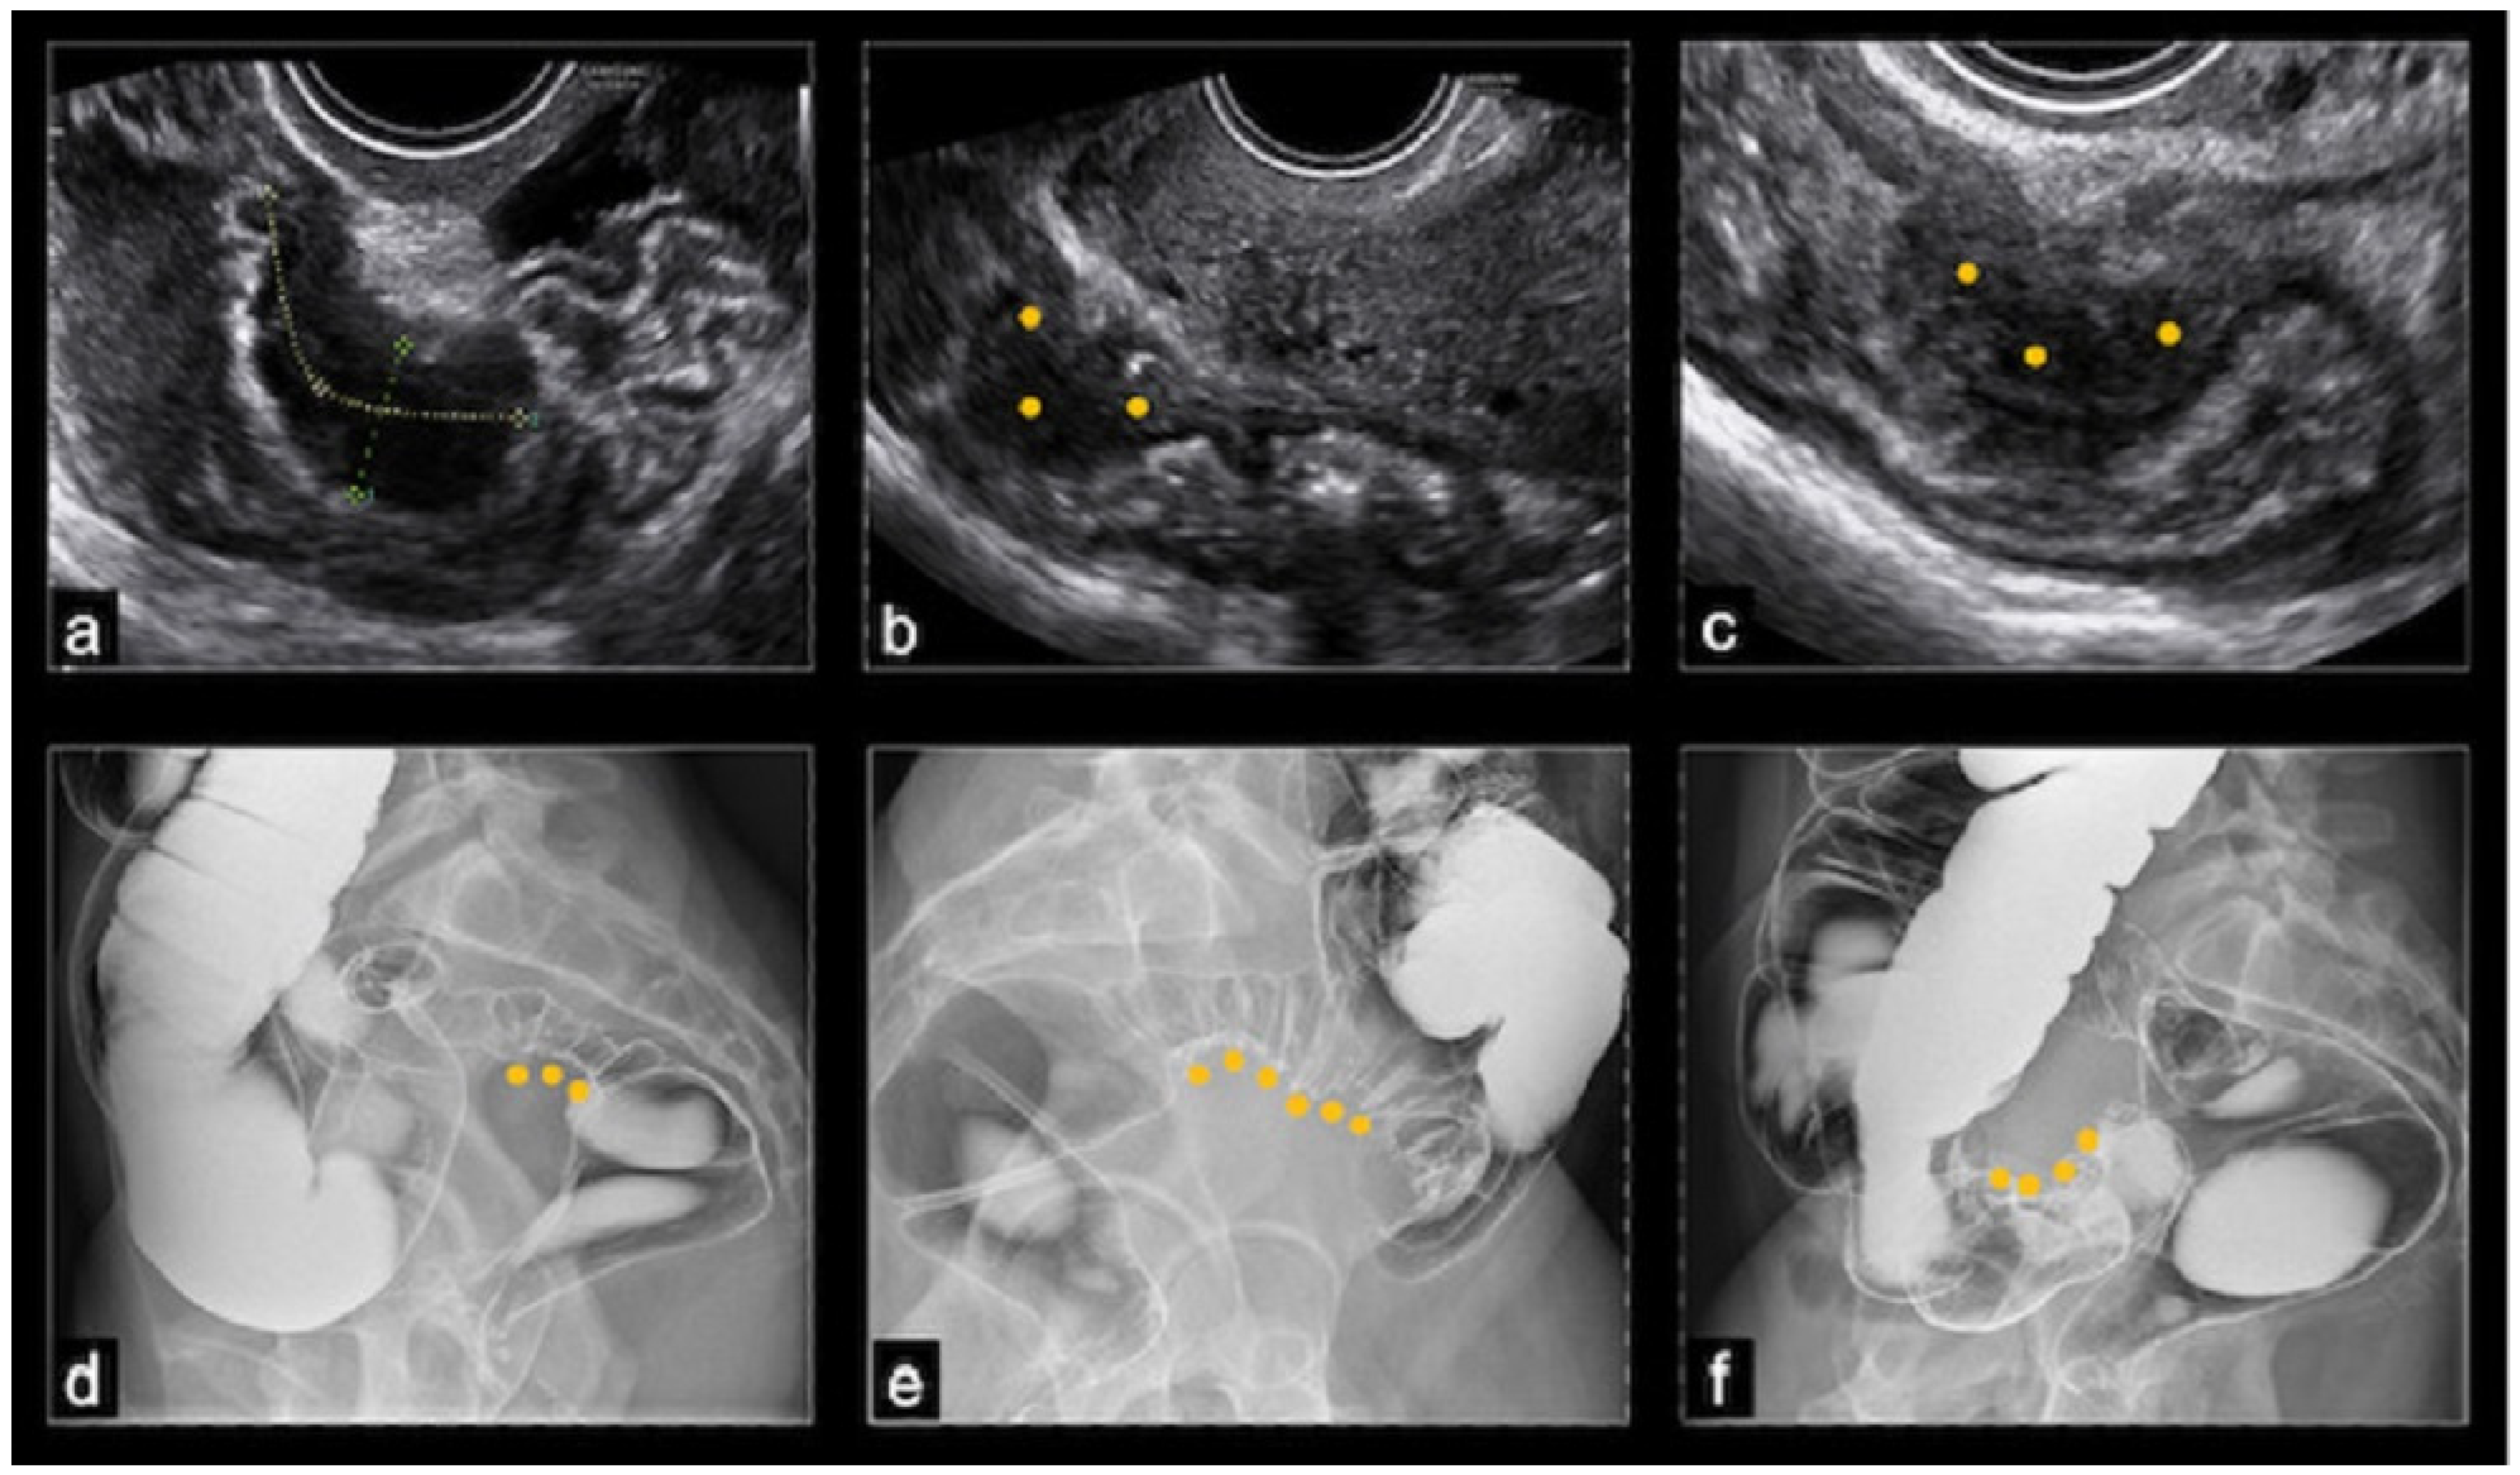

On ultrasound, BE typically appeared as a thickening of the hypoechoic muscularis propria or as hypoechoic nodules with irregular margins, without detectable blood flow on color Doppler. Nodules located above the level of the uterine fundus were considered sigmoid lesions, those at the level of the uterine fundus were denoted as rectosigmoid junction lesions, and those below this level were classified as rectal lesions. The dimensions of the nodules were recorded in three orthogonal planes; however, in this study, only the largest measurement was considered. The protrusion of a nodule toward the lumen of the bowel indicated the possibility of (sub)stenosis. The final nodule dimension was determined by averaging the dimensions reported by TVS and the DCBE, while the degree of stenosis was evaluated solely by the DCBE (Figure 1).

Figure 1.

(a–c) Ultrasonographic images of rectal nodules causing an estimated stenosis of 30–40%; (d) barium enema image of a recto-sigmoid junction nodule causing an estimated stenosis of 30–50%; (e) barium enema image of a sigmoid nodule causing an estimated stenosis greater than 50%; (f) barium enema image showing a cecal nodule.